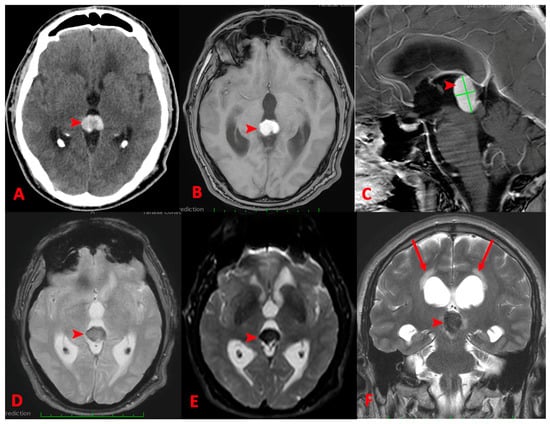

3.2.2. MRI

| Primary pineal melanoma | Extremely rare | Depending on the percent of melanin-containing cell: >10%—hyperintense on T1, hypointense on T2. <10%—hypointense on T1and hyperintense on T2. | |